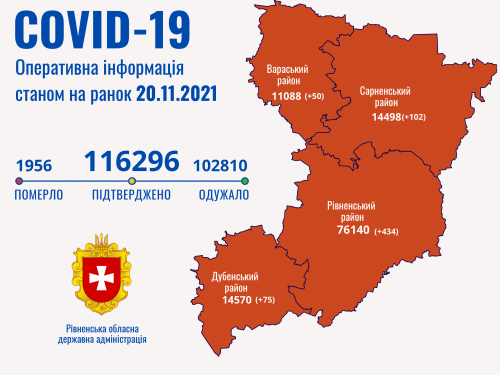

Коронавірус повертається: як стрімко зростає кількість хворих на Рівненщині (ВІДЕО)

Пів тисячі - у важкому стані, 9 жителів Рівненщини померли за добу від коронавірусу